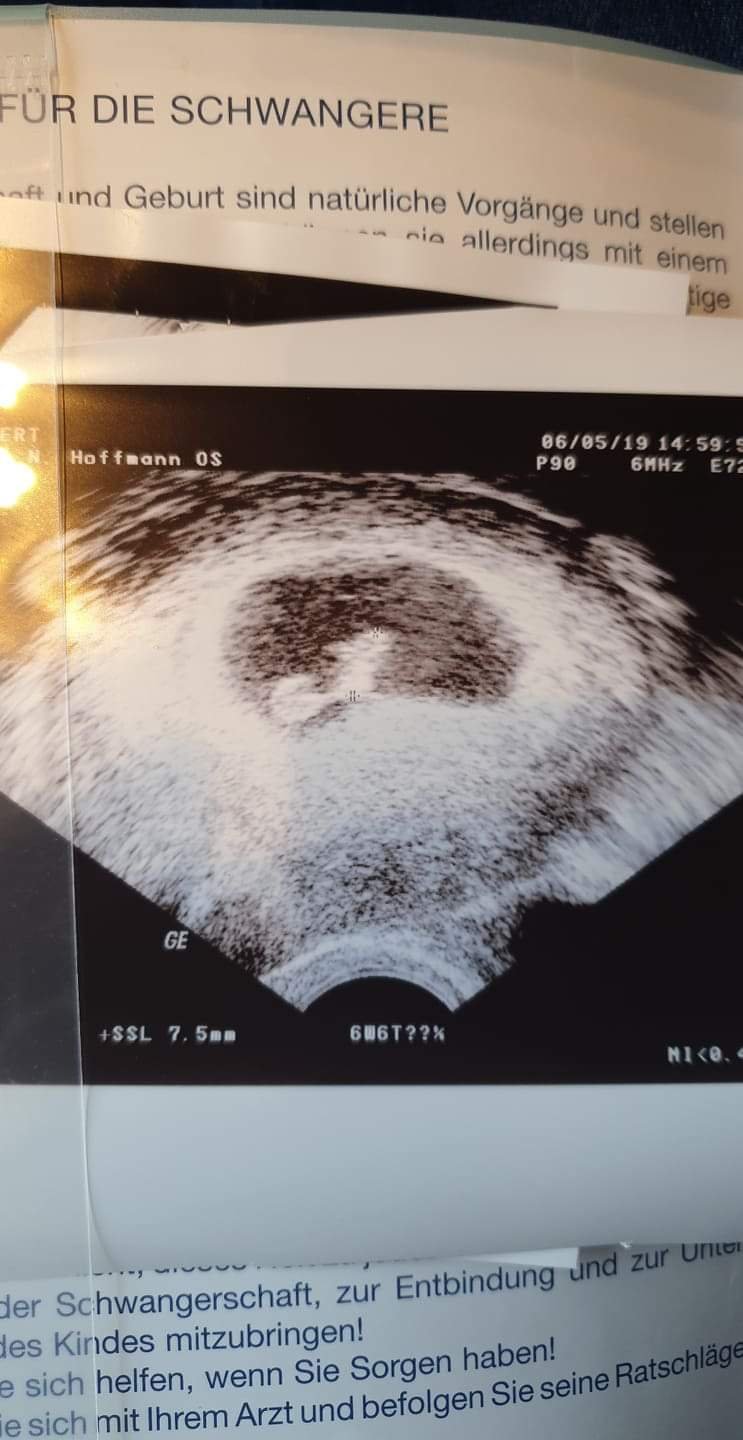

Hej dziewczyny ja juz po wizycie [emoji173]Serduszko widzialam jak bije ale nie słyszałam[emoji3059]. Dzieciatko 7,5mm 2 dni mlodsze jak i myslalam. Termin narazie z OM 22.12.Nastepna wizyta za 2 tyg. Zobacz załącznik 969489